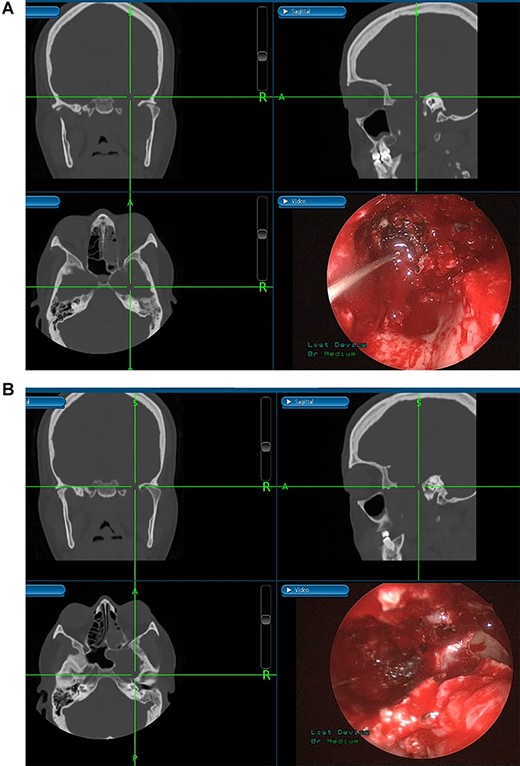

(A) Image-guided tumor removal from petrous carotid artery. (B) Image-guided intraoperative picture status post-complete tumor removal from trigeminal and middle cranial fossa.

The patient underwent an image-guided endonasal endoscopic tumor removal starting by endoscopic medial and posterior walls maxillectomies to control the tumor removal from the lateral sphenoid sinus and the infratemporal fossa after cauterization of the maxillary artery and sphenopalatine artery branches feeding the tumor. The tumor was dissected and removed from the cavernous (Fig. 3A) and petrous carotid artery in the middle cranial fossa (Fig. 3B). The middle cranial fossa’s dura was intact during the tumor removal (Fig. 3C). All the steps of tumor removal were controlled and monitored under image-guided navigation for accurate localization of tumor removal and avoidance of violation to the middle cranial fossa’s dura, or the brain, and the internal carotid artery in its cavernous and petrous segments (Fig. 4a and b).

Tumors in the infratemporal fossa require extensive approach such as middle fossa extraduaral approach, infratemporal fossa extradural approach, transmaxillary approach, transmandibular approach or transcervical approach. Complications from these procedures include cosmetic problems, facial nerve dysfunction, hearing loss and dental malocclusion. Image-guided endoscopic surgery allows for the preservation of intracranial structures, internal carotid artery and cranial nerves. Moreover, this procedure aids in rapid localization of the anatomical structures and meticulous intervention restricted to tumor margins. The screen is divided into four sections allowing visualization of the tumor from axial, coronal and sagittal views [10].